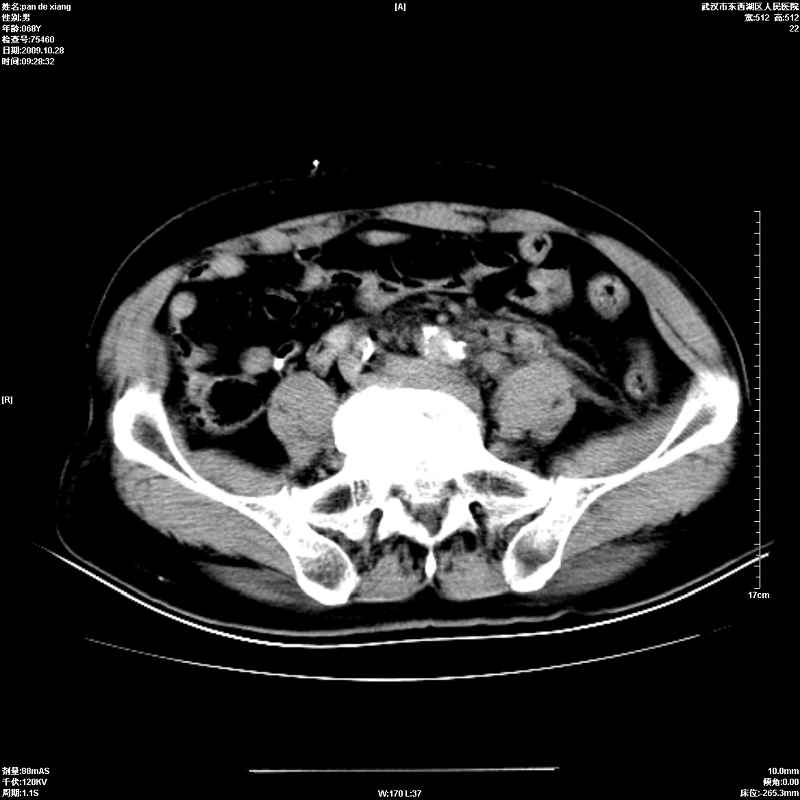

以下是引用杀毒软件在2009-10-28 20:41:00的发言:[br]结合临床考虑---白血病双肾改变或淋巴瘤。

以下是引用zxl51642在2009-10-29 9:59:00的发言:[br]结合临床“单克隆免疫球蛋白血症”,考虑双肾为继发损害并肾功能不全(尿中大量igg及少量iga、igm等大分子免疫球蛋白滤出所致继发损害),椎前软组织肿块为髓外造血。与浆细胞瘤有区别,平扫时有战友说的很清楚。